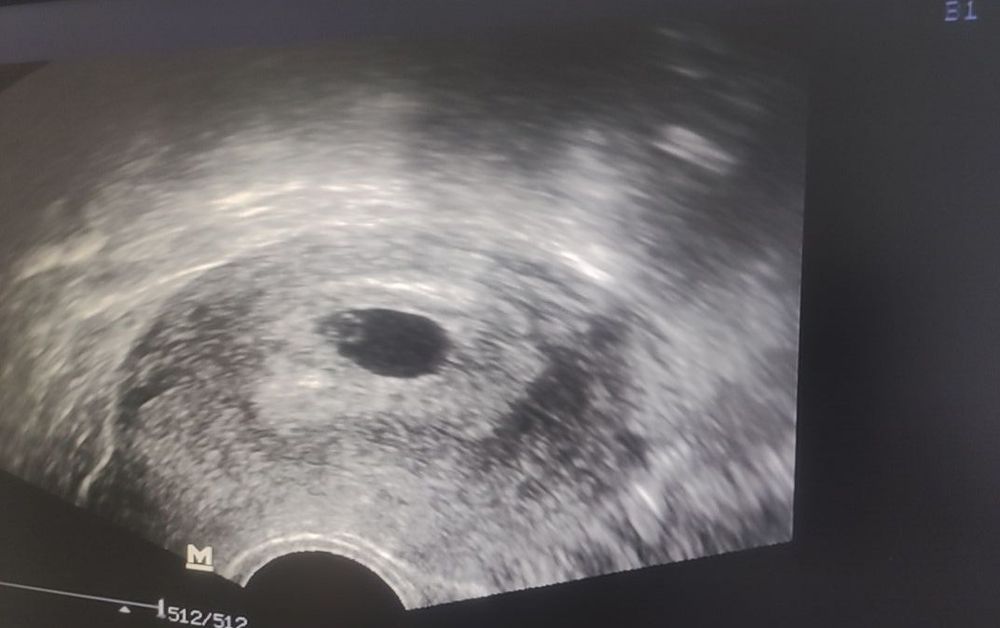

УЗИ 5нед 4д

Девочки всё отлично вроде))) ура!!!